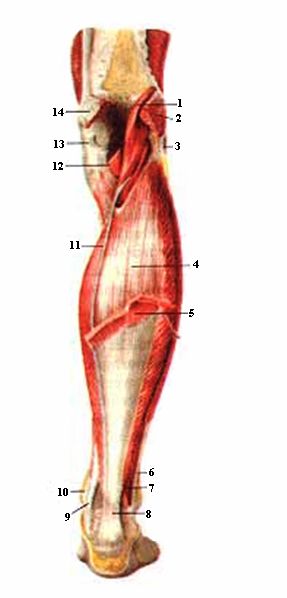

Анатомия подошвенной мышцы голени: подробное рассмотрение